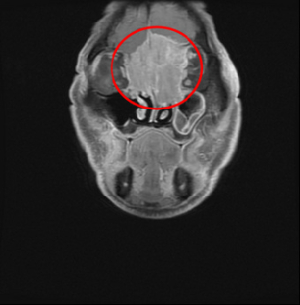

眼睛痛視力模糊 竟是非典型的嗅神經母細胞癌

79歲的黃先生兩年來時常感覺眼睛不舒服,原以為是針眼做怪,直到去年8月,突然雙眼看不清,才檢查出是顱底長腫瘤,進而轉到花蓮慈濟醫院耳鼻喉科,經詳細檢查為罕見「嗅神經母細胞癌」,周昱甫副主任與團隊隨即為他進行微創手術,取出6公分大的腫瘤,後續再以電療及化療清除殘餘癌細胞,目前黃先生已恢復良好,只需定期追蹤觀察。